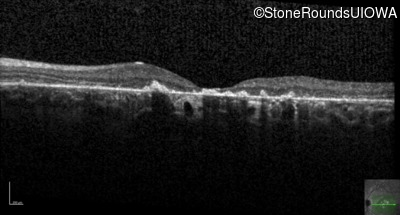

Age at visit: 26 years

Age at visit: 27 years

Age at visit: 31 years